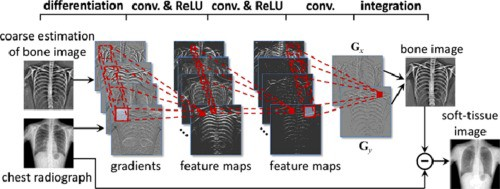

17年吴恩达团队发表了一篇论文:CheXNet: Radiologist-Level Pneumonia Detection on Chest X-Rays with Deep Learning,该论文提出CheXNet技术,即是一个使用ChestX-ray14数据集训练的121层的深度卷积网络,该网络通过胸片识别肺炎的准确率已经和人类放射科医生持平甚至更高。网络输入为人体正面扫描的胸片,输入时患肺炎的概率。该模型层结构复杂,数据量大,因此训练的模型比较精准。